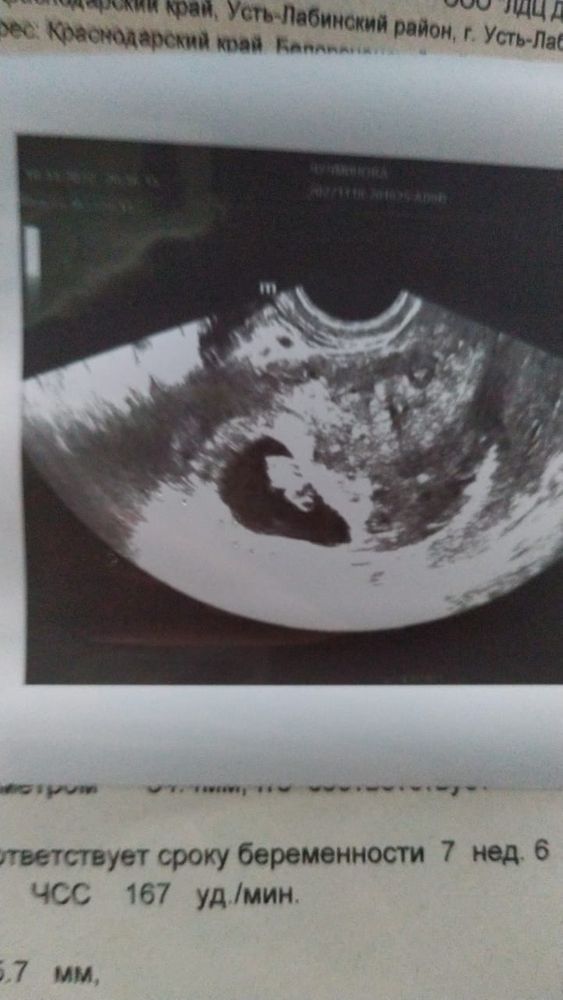

Ставят угрозу из-за неправильно формы места где находится ребенок, было у кого-то такое? Что делали? Это очень опасно?🙄

В ожидании чудес, да, всё хорошо, только форма плодового яйца неправильной овоидной формы